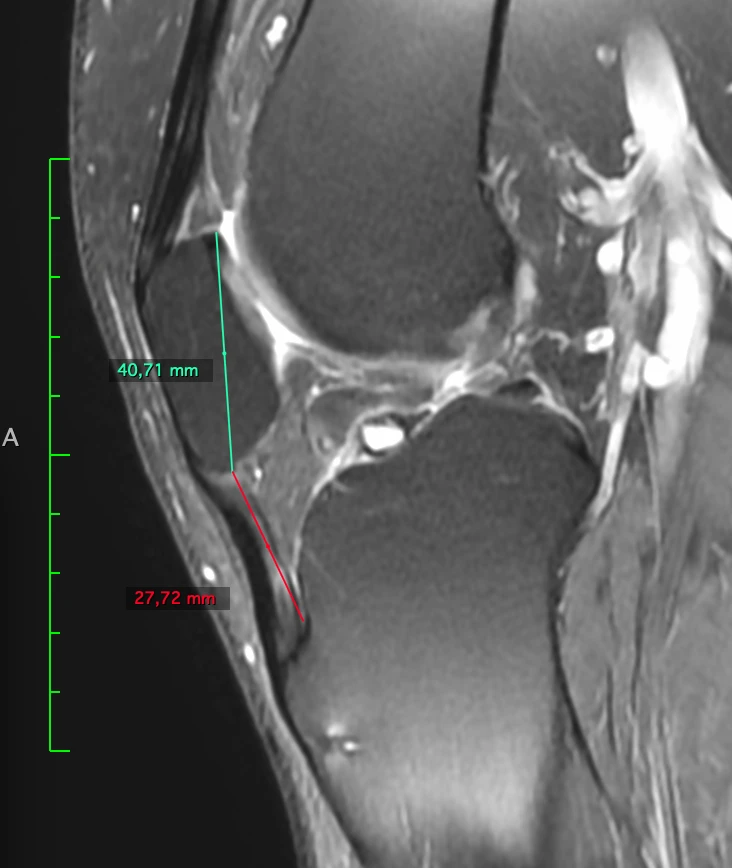

Patella baja и лигаментоз собственной связки надколенника вследствие этого.

👍 38